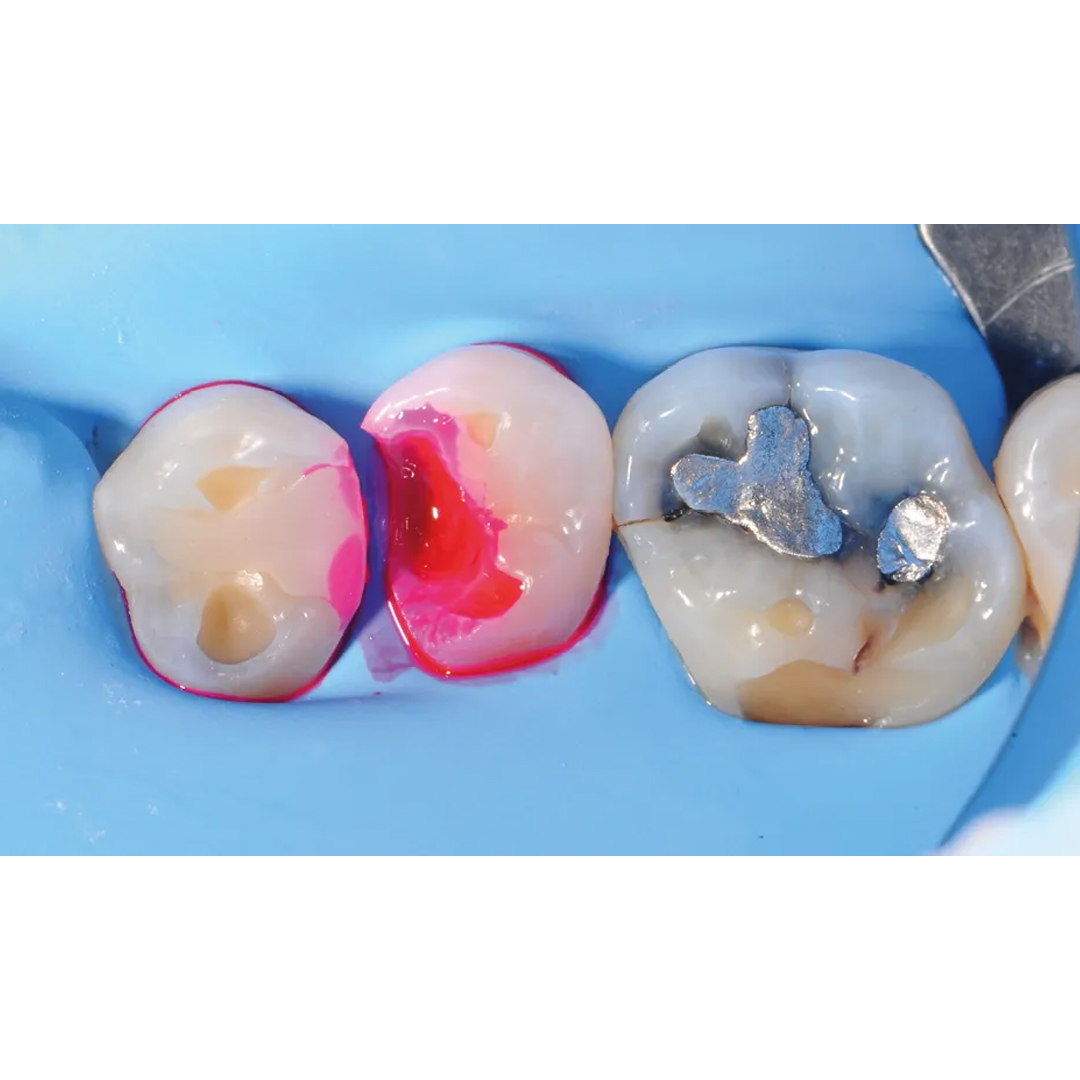

Chairside materials - caries detector, teethmate™ f-1 2.0